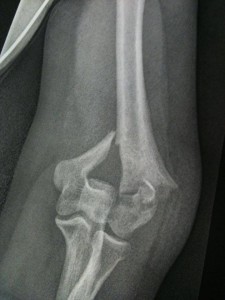

Well my streak ended this Saturday when I smashed my funny bone against an icy sidewalk.

That’s when I felt the bone sticking at an odd angle just above my elbow. My arm is broken, came my surprisingly rational thoughts. Should I walk the few houses back to my house or knock on a neighbour’s door? And then I screamed. I screamed and screamed and screamed.

I gingerly removed my coat for the triage nurses in emergency, then sat for a long time on a stretcher in the corridor, my concerned husband at my side. I was thirstier than I’ve ever been, but was not allowed water in case they had to put me under. Eventually I was given a morphine drip that made me sleepy then sent down the hall to have my arm X-rayed. Given where the break was, the X-ray tech was surprised I wasn’t screaming. But I’d been there for hours and there’s only so long one can scream.

I’m not sure how much time went by. Time passes differently in the hospital. Time passes differently when you’re in pain. Sometime later they put me to sleep and set my arm. It was a temporary fix and I still needed surgery. My arm hurt whenever I moved any part of my body.

Eventually I got moved into a room which I shared with an 83-year-old Italian-Scottish woman whose hip was being replaced. My friend Becca came and brought me Star Trek, a much better pain killer than whatever was in my IV. An orthopedic surgeon talked to me about the surgery he was going to do, which involved drills and saws and permanently installed titanium plates and screws.

On Sunday I was in surgery for at least four hours (my Mom says it was more like five). This passed for me in one slow eye-blink. When it was over my arm felt better than before, not awesome but better. It was secure in its part-hard part-soft cast. I no longer felt my bones grinding against each other whenever I moved.